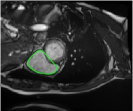

4.3 Comparison with cardic MR images for right ventricle segmentation

Cardiac MRI images often suffer from intensity inhomogeneity due to the varying magnetic susceptibility of cardiac tissues. This can lead to ambiguous boundaries, making it hard for models to consistently identify the left ventricle. Moreover, the heart is composed of several complex anatomical structures, including chambers, valves, and surrounding tissues. Accurately delineating the borders between these various components can be difficult, especially when they are closely positioned or exhibit similar intensity characteristics. In this section, we demonstrate the effectiveness of the RefLSM in segmenting cardiac MR images. The cardiac MR images are standardized to a size of . To enhance the credibility of the proposed model, we segmented 5 cardiac MR images compared the results with 6 other models, including the ALF [MA2019201], LoGRSF [DING2017224], ABC [WENG2021115633], RESLS[8765635], ICTM [WANG2022108794] and FeaACM [XUE2024110673] models. Fig. 5 displays the partial results from all the segmentation models. It is clear that the segmentation results from the RefLSM closely align with the ground truth of the left ventricle segmentation. However, the ALF model demonstrates relatively poor ability to capture the overall structure of the left ventricle; it exhibits limitations with precise boundary detection, particularly in areas of intensity inhomogeneity. Consequently, the evolution curve of the ALF fits into an unstable wave-like result. Suffering from intensity inhomogeneity and surrounding anatomical structures, the LoGRSF model, ABC model and RESLS model all represent over-segmentation and under-segmentation to some extent. Additionally, the results in the 6th column of Fig. 5 show multiple instances where where the ICTM model inaccurately identifies adjacent myocardial tissues as part of the left ventricle due to their similar intensity, leading to false positives. While the FeaACM demonstrates some ability to segment the left ventricle, it is not robust and fails to segment the 5th row of Fig. 5. The 2nd and 3rd rows also include small adjacent excessive regions. In contrast, our proposed model demonstrates marked improvements in accurately capturing the left ventricle’s boundaries. It effectively addresses challenges associated with severe intensity inhomogeneity and noise, resulting in better segmentations. The proposed method appear to maintain better structural integrity in the segmented images, closely aligning with the ground truth.

To quantitatively measure the segmentation results of each model, we compute the Dice and Precision values for left ventricle segmentation. Moreover, we opted for a voilin plot to effectively compare the RefLSM with six other models, as shown in Fig. 7. The results clearly demonstrate that the RefLSM yields superior Dice and Precision values than the other representative models, indicating its closer alignment with the ground truth and highest segmentation accuracy.